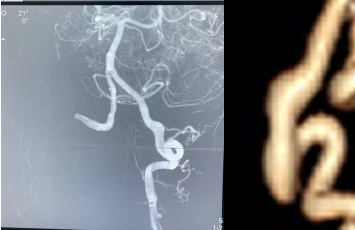

患者薛阿姨为72岁女性,因突发左侧颈后部1月余,呈搏动性疼痛,考虑为神经性疼痛,经积极治疗后无明显缓解。疼痛发作时夜不能寐,不思饮食,非常痛苦。患者听闻医院有北京专家长期坐诊,遂来我院寻求帮助。脑外科田垒医生接诊患者后建议患者入院治疗。入院后查体,患者神志清楚,对答切题,四肢活动好,无其他异常。董永军副主任查看患者后考虑为“脑血管疾病”,进一步行全脑血管造影明确诊断为“左侧椎动脉V4段夹层动脉瘤”。血管迂曲严重,椎动脉夹层动脉瘤所处位置在脑干附近,动脉瘤最宽处直径约7mm,长约2cm,一旦破裂凶多吉少。

术前